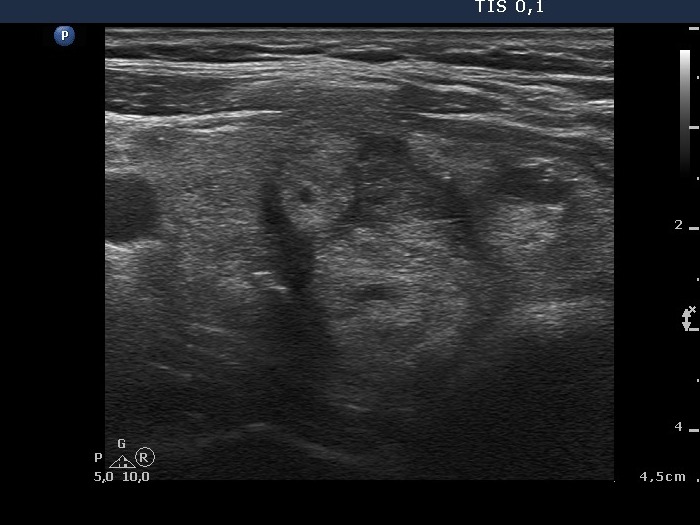

Follow-up investigation 8 month later (second row of images)

Clinical data: the patient had no complaints.

Palpation: the nodule in the right lobe was significantly smaller compared with first examination.

Functional state: euthyroidism (TSH 0.96 mIU/L).

Ultrasonography. The thyroid was echonormal. The nodule was composed of multiple echonormal discrete lesion and lacked cystic fluid. The volume was 1/8 of the pretreatment size.

Suggestion: yearly follow-up.